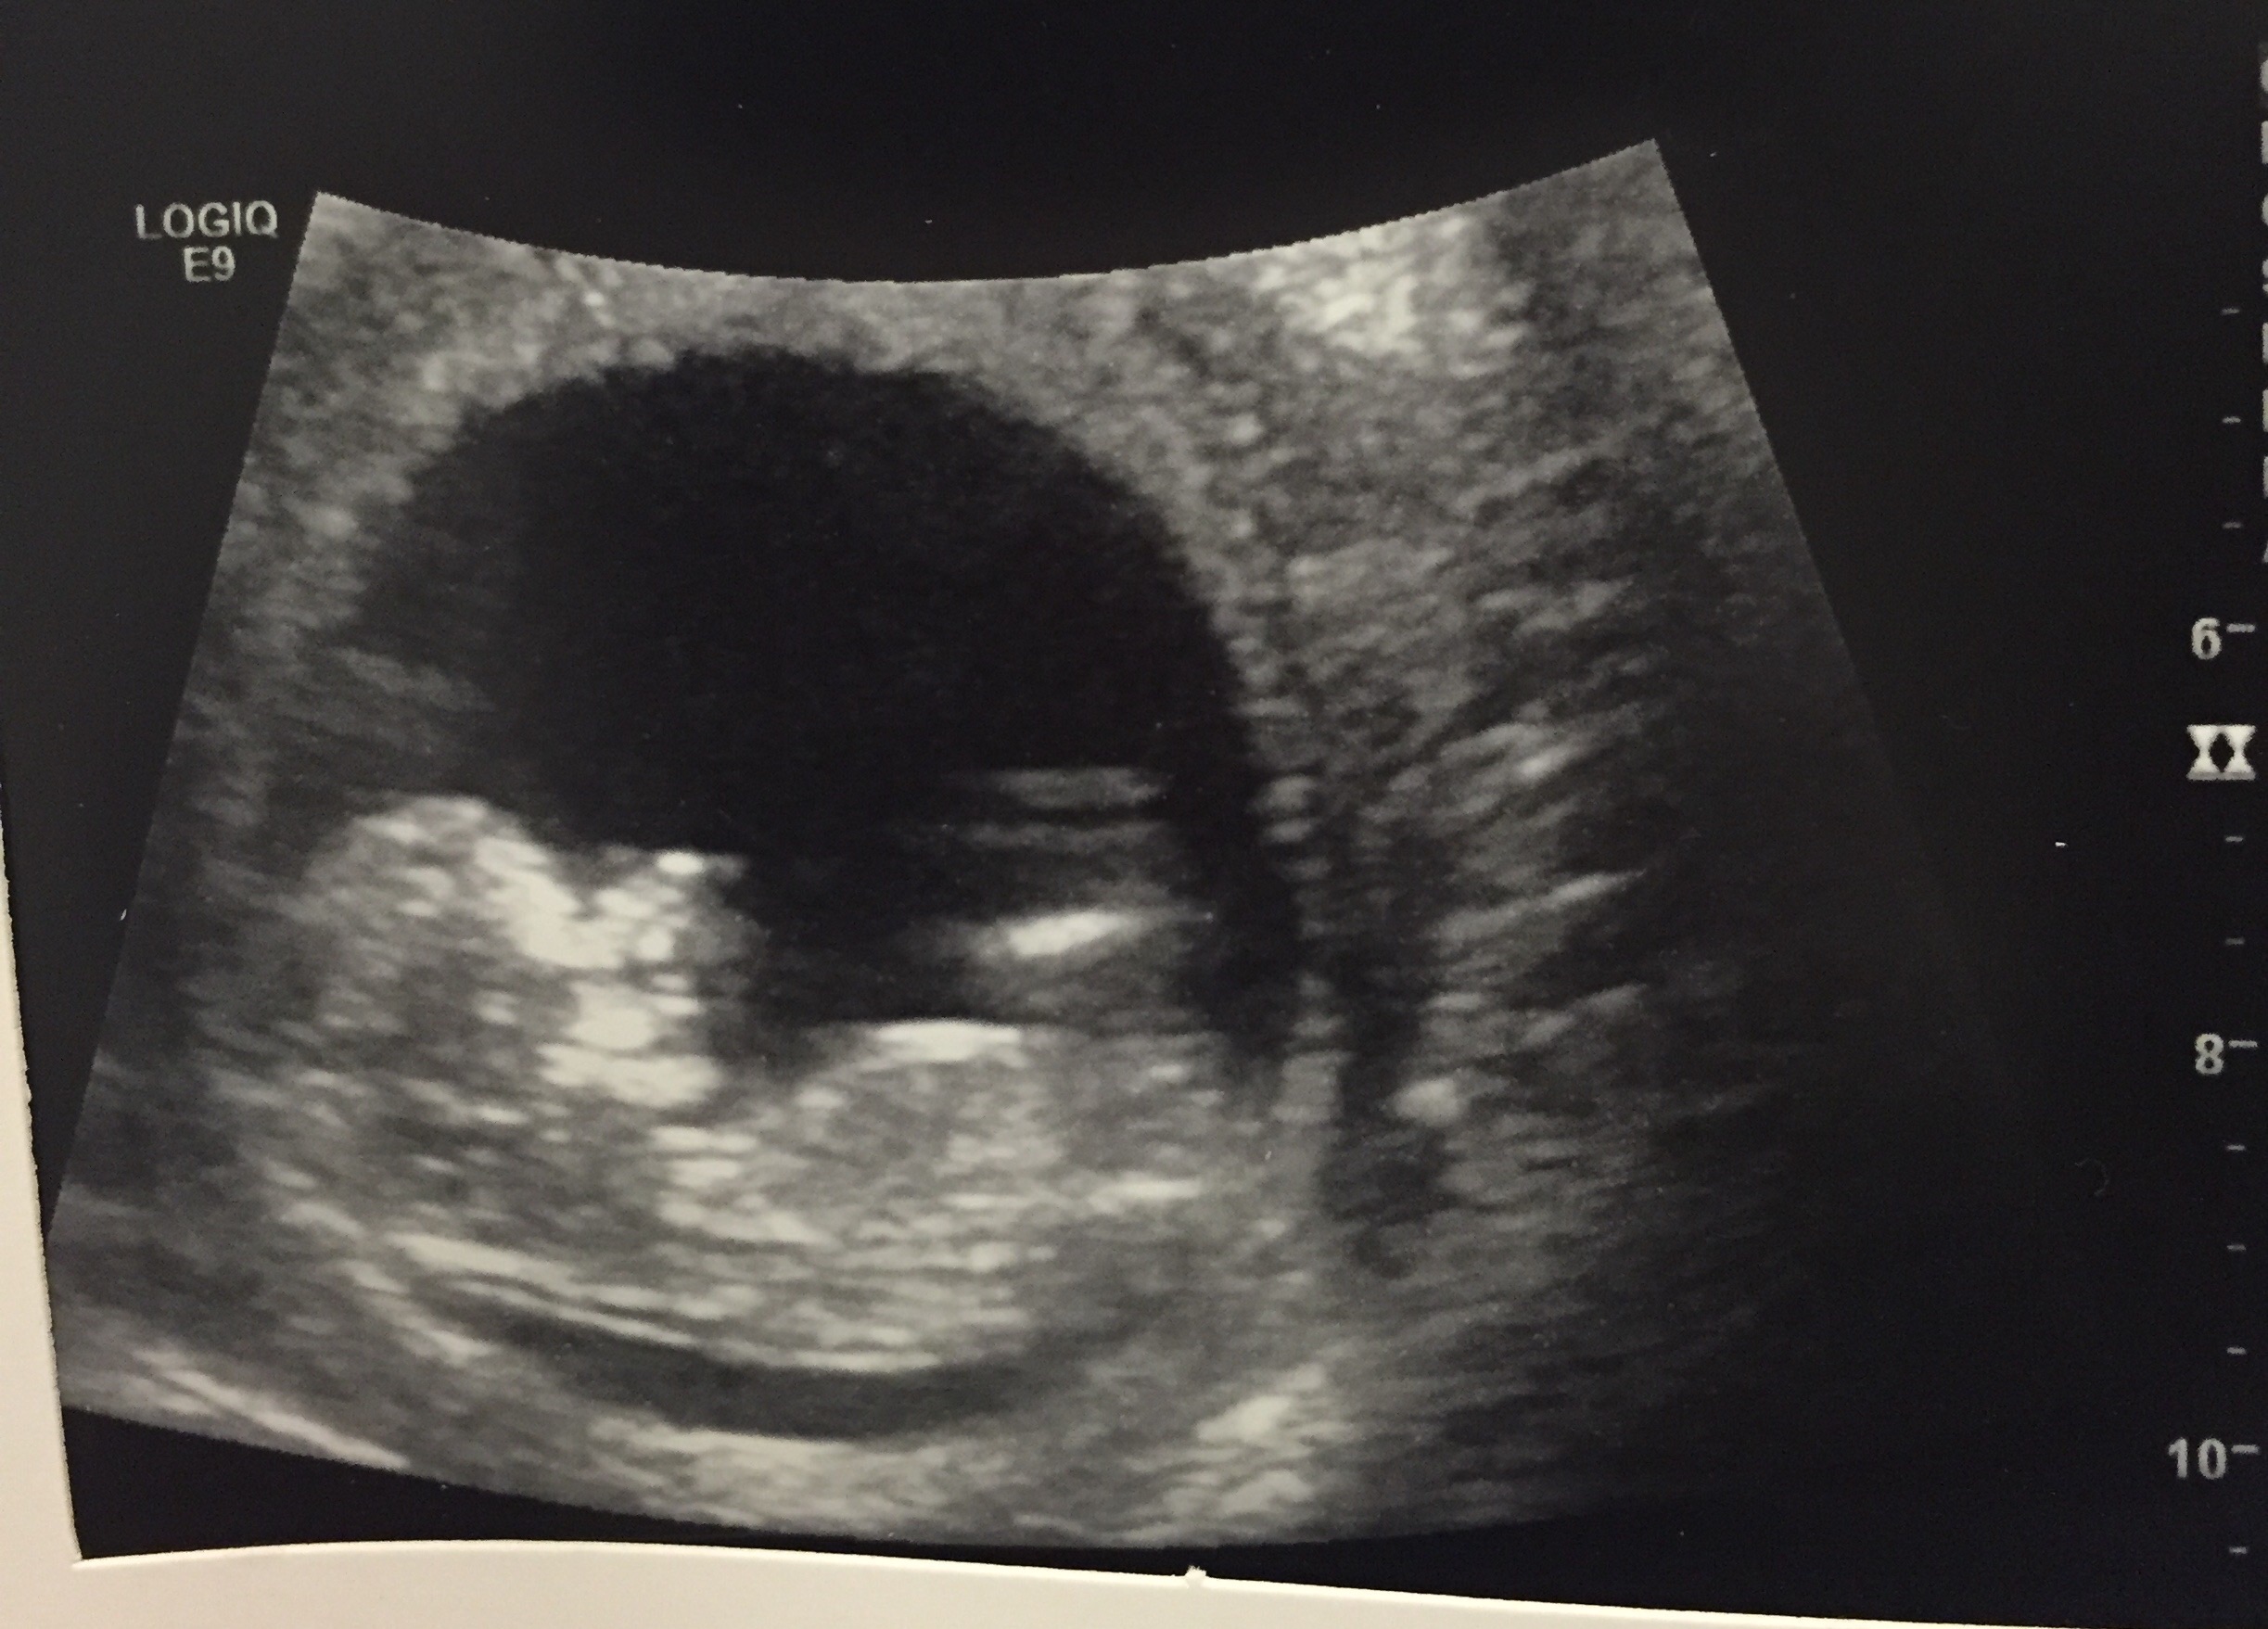

Nub theory 12+1 girl or boy?

Can anyone tell me if they think i am having a girl or boy